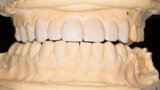

Fig. 5: Functional analysis wax-up.